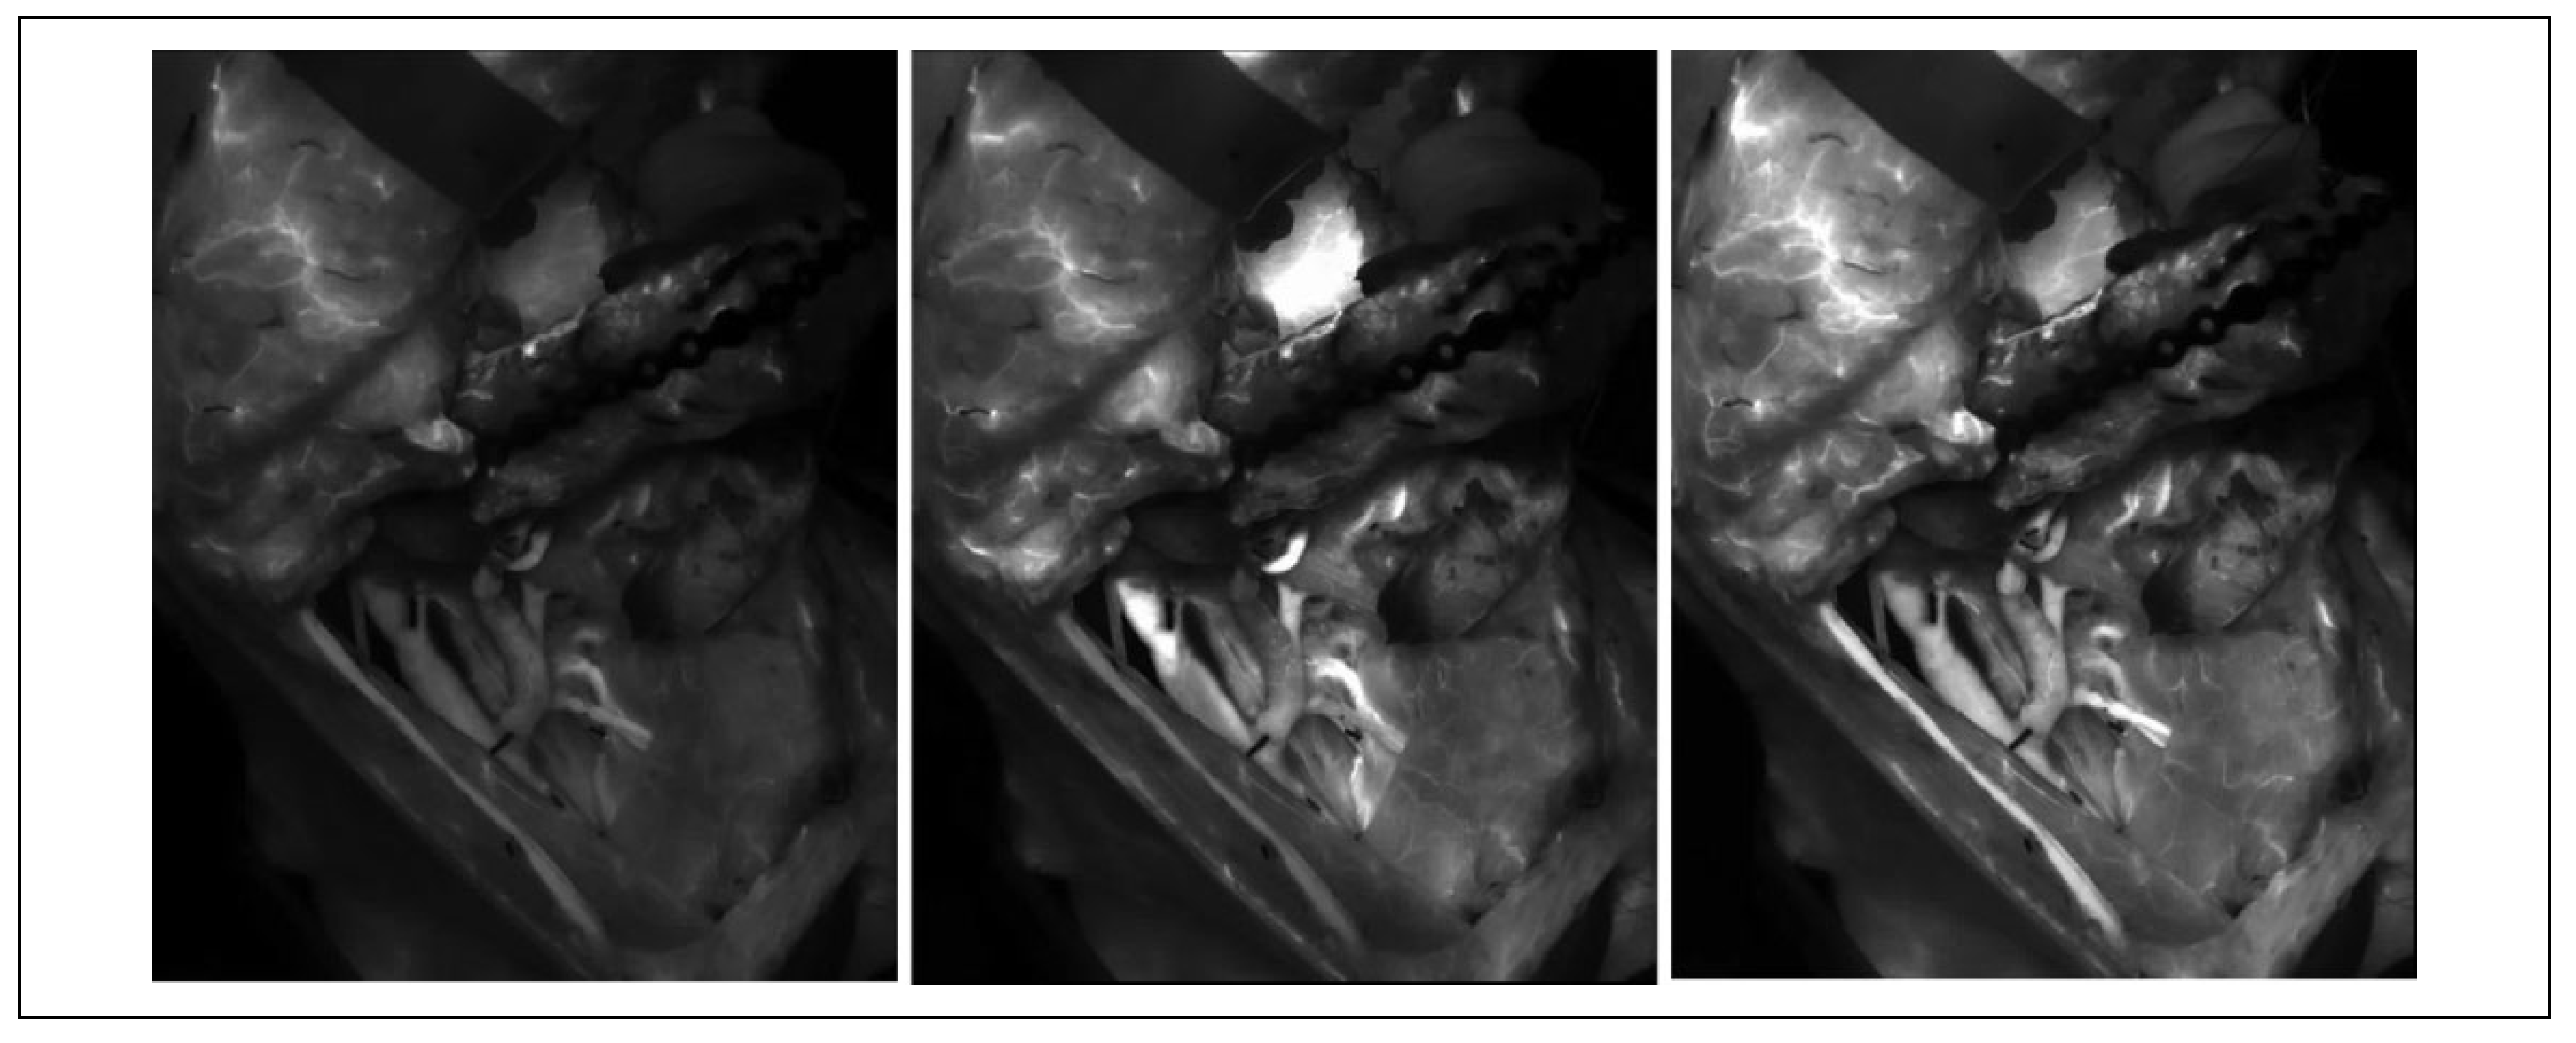

Intraoperative evaluation of free flap perfusion has been developed to identify and correct vessel occlusion as well as guide clinical decisions as to the need for flap revision or tissue resection. Clinical judgment further provides relevant information to assess the degree of tissue perfusion, however variation in anatomic location of perforating vessels and perfusion zones complicating flap design calls for more sophisticated methods to assess perfusion. Fluorescein dye was historically utilized to evaluate perfusion and ultimately allowed for other fluorescent agents to be developed.[17,18,19,20] Laser angiography using indocyanine green (LA-ICG) is able to assess vascularity in the recipient site as well as circulation and perfusion in free or pedicled flaps (Figure 1).[21,22,23] Laser angiography using indocyanine green remains in the intravascular space for about 3 to 5 minutes, allowing for multiple doses during a single surgery—an improvement from fluorescein which cannot be used repeatedly.[24] SPY Elite system (LifeCell Corp; manufactured by Novadaq Technologies Inc) is a near-infrared video camera system used for LA-ICG angiography, which utilizes filters to detect fluorescent signals in vessels with diameters as small as 1 mm when integrated into the optical path of a surgical microscope.[24,25] This allows for a high magnification to visualize the anastomosis and overall greater predictability of adequate perfusion.

Figure 1. Snapshots through time of indocyanine green flowing across the anastomotic site in the neck to a fibula free flap visualized using the SPY system. Image on left occurs at beginning of injection of indocyanine green, and next 2 images to the right demonstrate perfusion to the flap as time passes. Perfusion is correlated with fluorescence on the image.